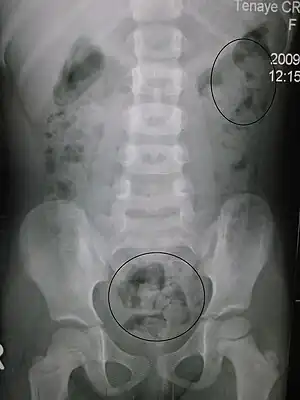

Constipation in a young child seen on X-ray. Circles represent areas of fecal matter (stool is white surrounded by black bowel gas).

Abdominal X-rays are generally only performed if bowel obstruction is suspected, may reveal extensive impacted fecal matter in the colon, and may confirm or rule out other causes of similar symptoms.[25][17]